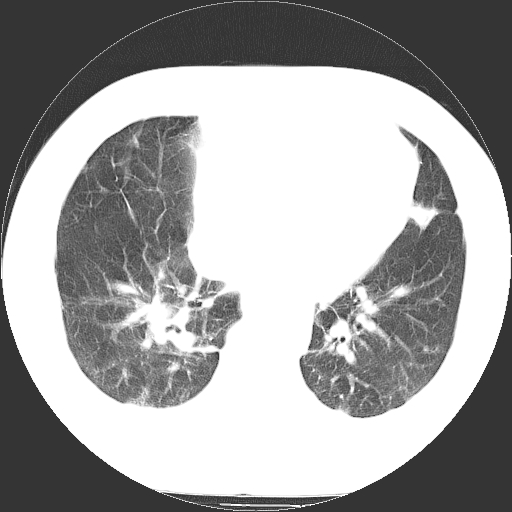

标题: CT21804:男,65岁,咳嗽、咳痰、发热5天。 [打印本页]

男,65岁,咳嗽、咳痰、发热5天。

支气管扩张合并感染,胸膜肥厚

两肺间质纤维化,支扩合并感染,双侧胸腔积液

支持慢性支气管、肺间质纤维化合并感染。

慢性支气管炎并感染,支扩,双侧少量胸腔积液.